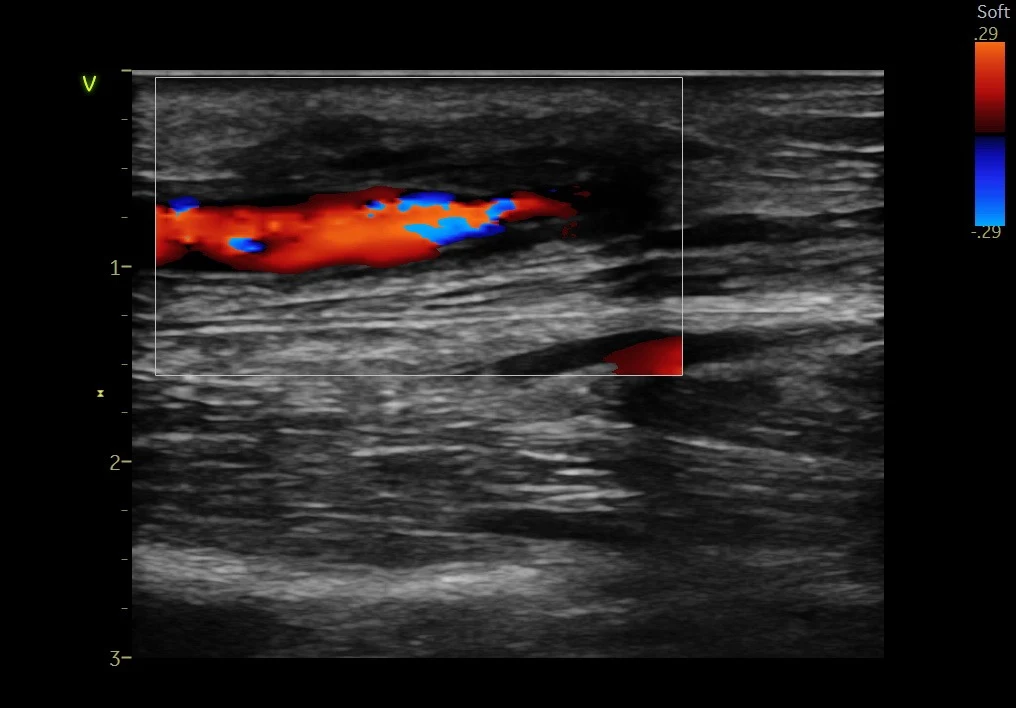

Fistula narrowing or blockage with facial swelling (central vein occlusion) and abnormal flow.

Restoring blood flow in blocked or dysfunctional AV fistulas.

Detailed evaluation with ultrasound or imaging to clearly identify the problem.